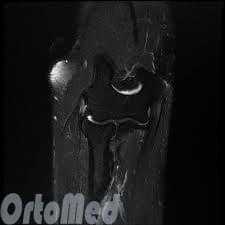

Магнитно-резонансная томография (МРТ) четко показывает мягкие ткани: измененные сухожилия, воспаленные участки.

Диагноз медиальный эпикондилит устанавливается на основании клинических признаков и характерного анамнеза. Для исключения костно-суставной патологии проводится рентгенография локтевого сустава в двух проекциях. Дифференциальная диагностика осуществляется с повреждением связок (разрывом или растяжением локтевой коллатеральной связки), медиальной нестабильностью локтевого сустава, шейной радикулопатией и синдромом кубитального канала. Для оценки состояния сухожильно-связочного аппарата назначается МРТ локтевого сустава, для уточнения состояния мышц - электромиография, для исключения нарушений со стороны нервной системы - консультация невролога и детальное неврологическое исследование.